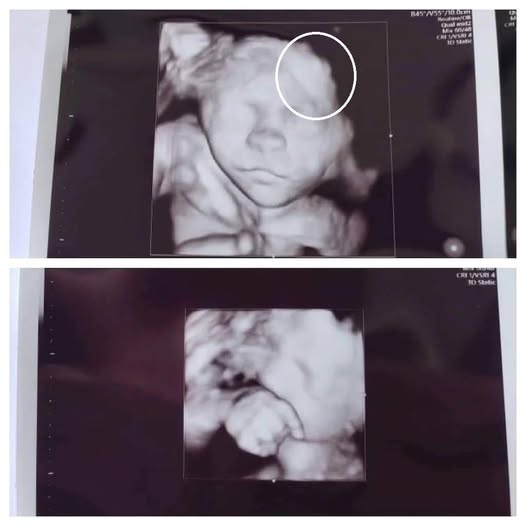

The technician, maintaining calm professionalism, informed the family that the image had shown something unusual that required further evaluation. While they did not immediately disclose details, the brief silence in the room left both mother and daughter unsettled. Staff assured them that unclear images are common—ultrasounds can sometimes capture shadows, angles, or movements that look concerning but turn out to be harmless upon review.

Doctors later explained that the initial scan had displayed an unexpected shape next to the developing baby, prompting the need for additional imaging. After a follow-up exam, they determined it was a benign artifact—a harmless visual distortion caused by the baby’s position and the machine’s angle. The clarification brought immense relief to both women, who had been preparing themselves for difficult news.